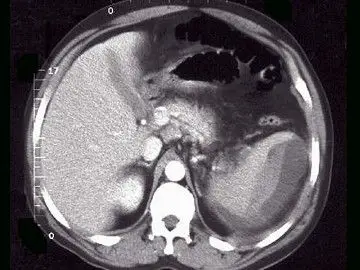

外伤4天复查,脾破裂

a,脾破裂实质内血肿 b,脾包膜下血肿 c,脾挫裂伤 d,脾梗死 e,脾扭转